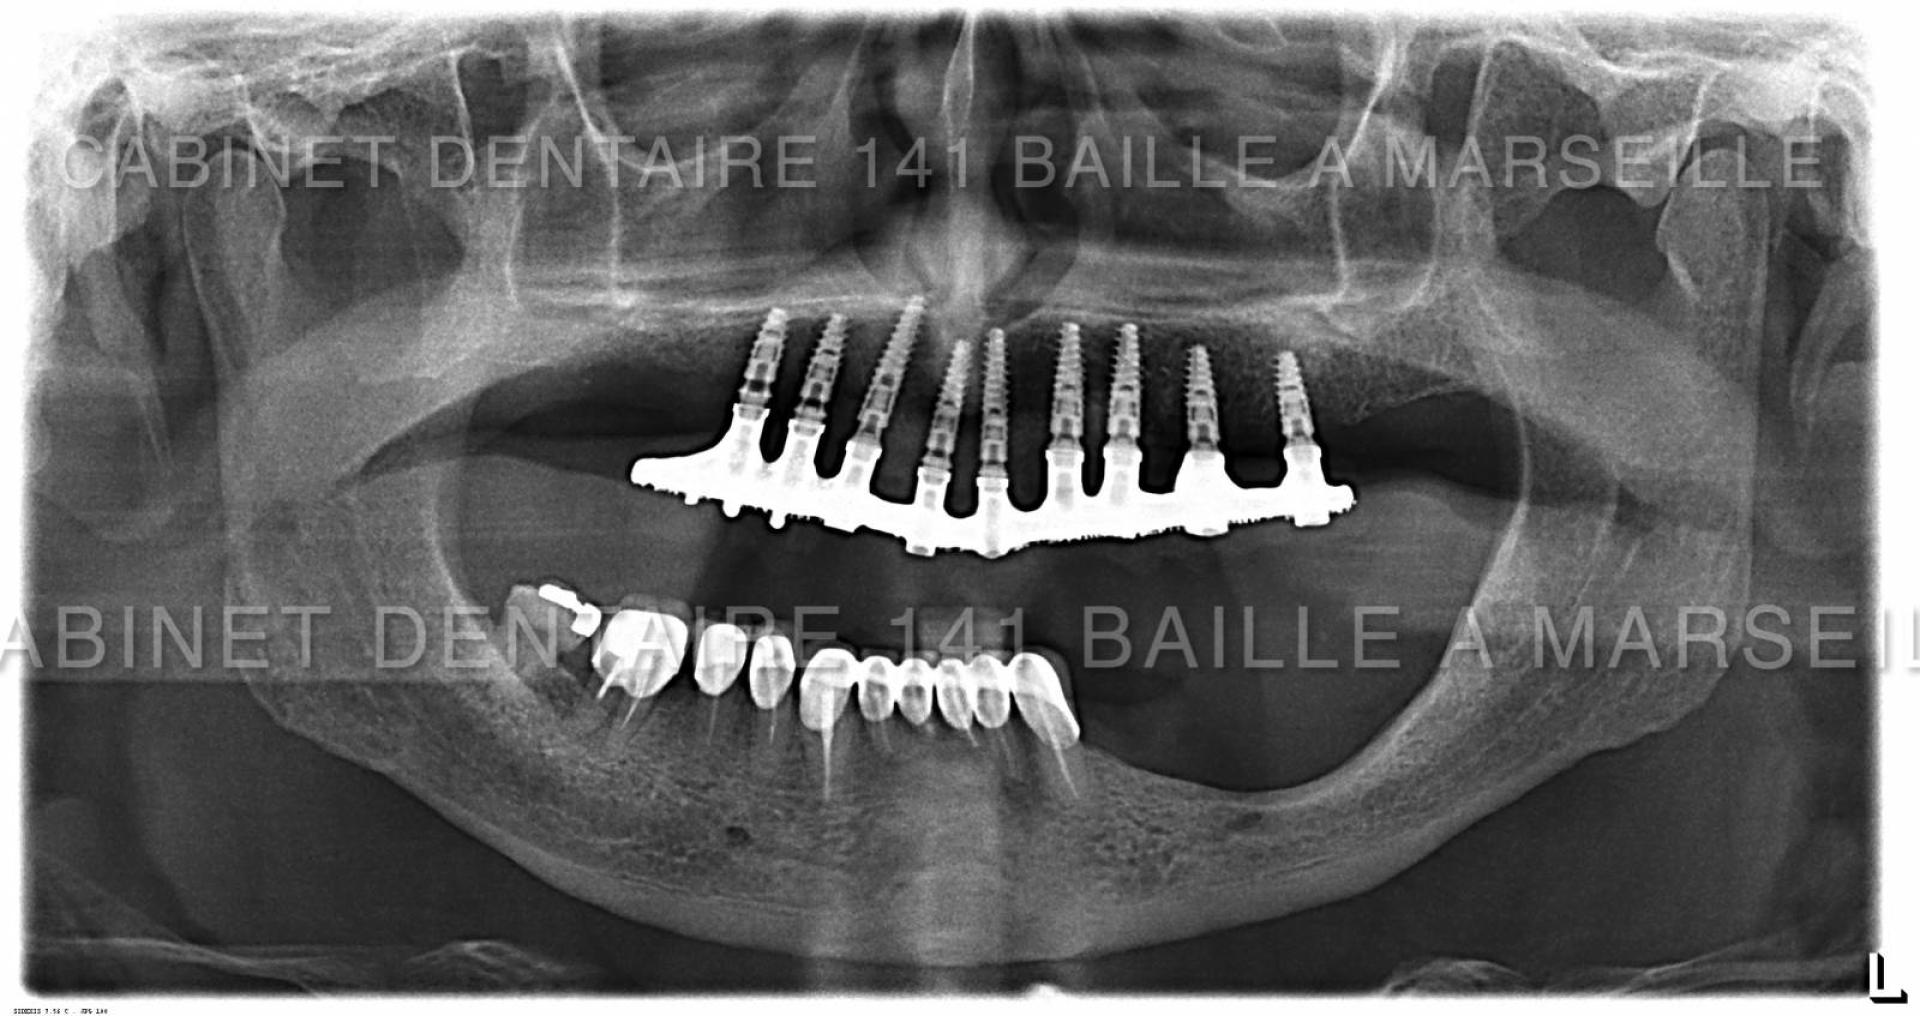

Nous sommes en mesure d'assurer la prise en charge de vos patients dans notre structure qui englobe la phase chirurgicale traitée naturellement en bloc opératoire stérile ,et sytème de traçabilité chirugicale aux normes hospitalières (Cycles prions à fractionnement de vide) ,pour tous les cas complexes intégrant implantations totales avec mise en charge immédiate.

Notre laboratoire intégré nous délivrera une prothèse immédiate qui permettra à votre patient de na pas avoir de gêne au niveau de sa vie sociale.

En général nous commençons à opérer le matin vers 9 h et la patient rentre chez lui vers 13h équipé d'une prothèse immédiate implanto- portée.